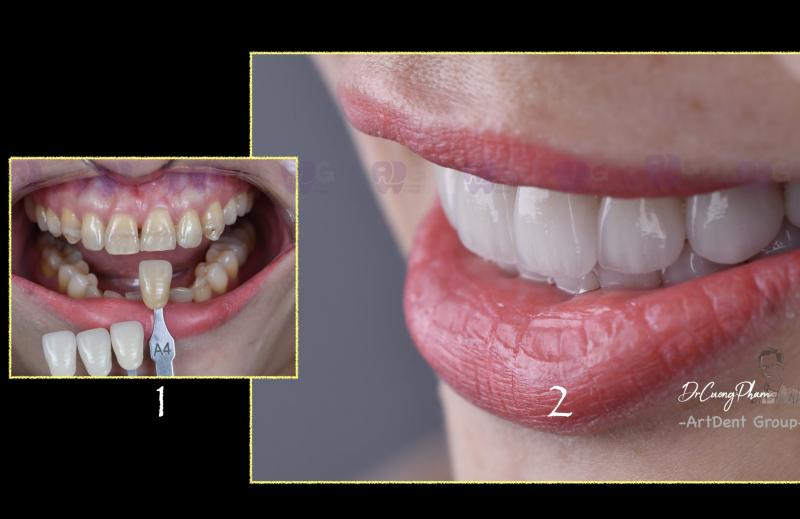

Nha Khoa Artdent Group

Gọi điệnNha Khoa Artdent Group – Địa chỉ chăm sóc răng miệng uy tín bậc nhất tại phường Tân Định, TP.HCM, là nơi quy tụ đội ngũ bác sĩ Răng Hàm Mặt chính quy được đào tạo bài bản từ Trường Đại học Y Dược TP.HCM. Với sứ mệnh “Kiến tạo nụ cười chuẩn y khoa”, Artdent không ngừng khẳng định vị thế bằng chất lượng chuyên môn, dịch vụ tận tâm và môi trường điều trị hiện đại, an toàn tuyệt đối.

Điểm nổi bật tạo nên sự khác biệt cho Artdent Group chính là hệ thống máy móc, thiết bị tân tiến bậc nhất cùng quy trình vô trùng đạt chuẩn quốc tế. Phòng khám cam kết chỉ sử dụng vật liệu cao cấp chính hãng từ các tập đoàn nha khoa hàng đầu thế giới như: 3M - Hoa Kỳ, KaVo Kerr - Đức, GC - Nhật Bản, Nobel Biocare - Thụy Sĩ, Ivoclar Vivadent - Liechtenstein.

- Dán sứ Veneer thẩm mỹ